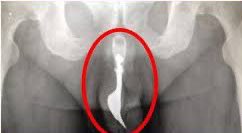

أخر حادثه مسجلة كانت في 1997 لرجل تبول في المياه وتطلب الامر عملية جراحية خطرة لإزالة السمكة من داخل مجرى البول

وكما هو الحال مع جميع الطفيليات، فإن سمكة الكانديرو تعيش على مضيفها، تلتصق بخياشيم الأسماك الكبيرة ويستنزفون فريستهم مما يسبب لها الالتهاب والنزيف ثم الموت.

هناك عدد من القصص عن هذه السمكة التي تسبح داخل مجرى البول البشري. لحسن الحظ انها حالات قليلة جدا من السكان المحليين

وهذا هو النوع الوحيد الذي من الممكن أن يستهدف مجرى البول بسبب حجمه الصغير ، أما باقي الانواع كبيرة الحجم نسبيا ومفترسة للأسماك